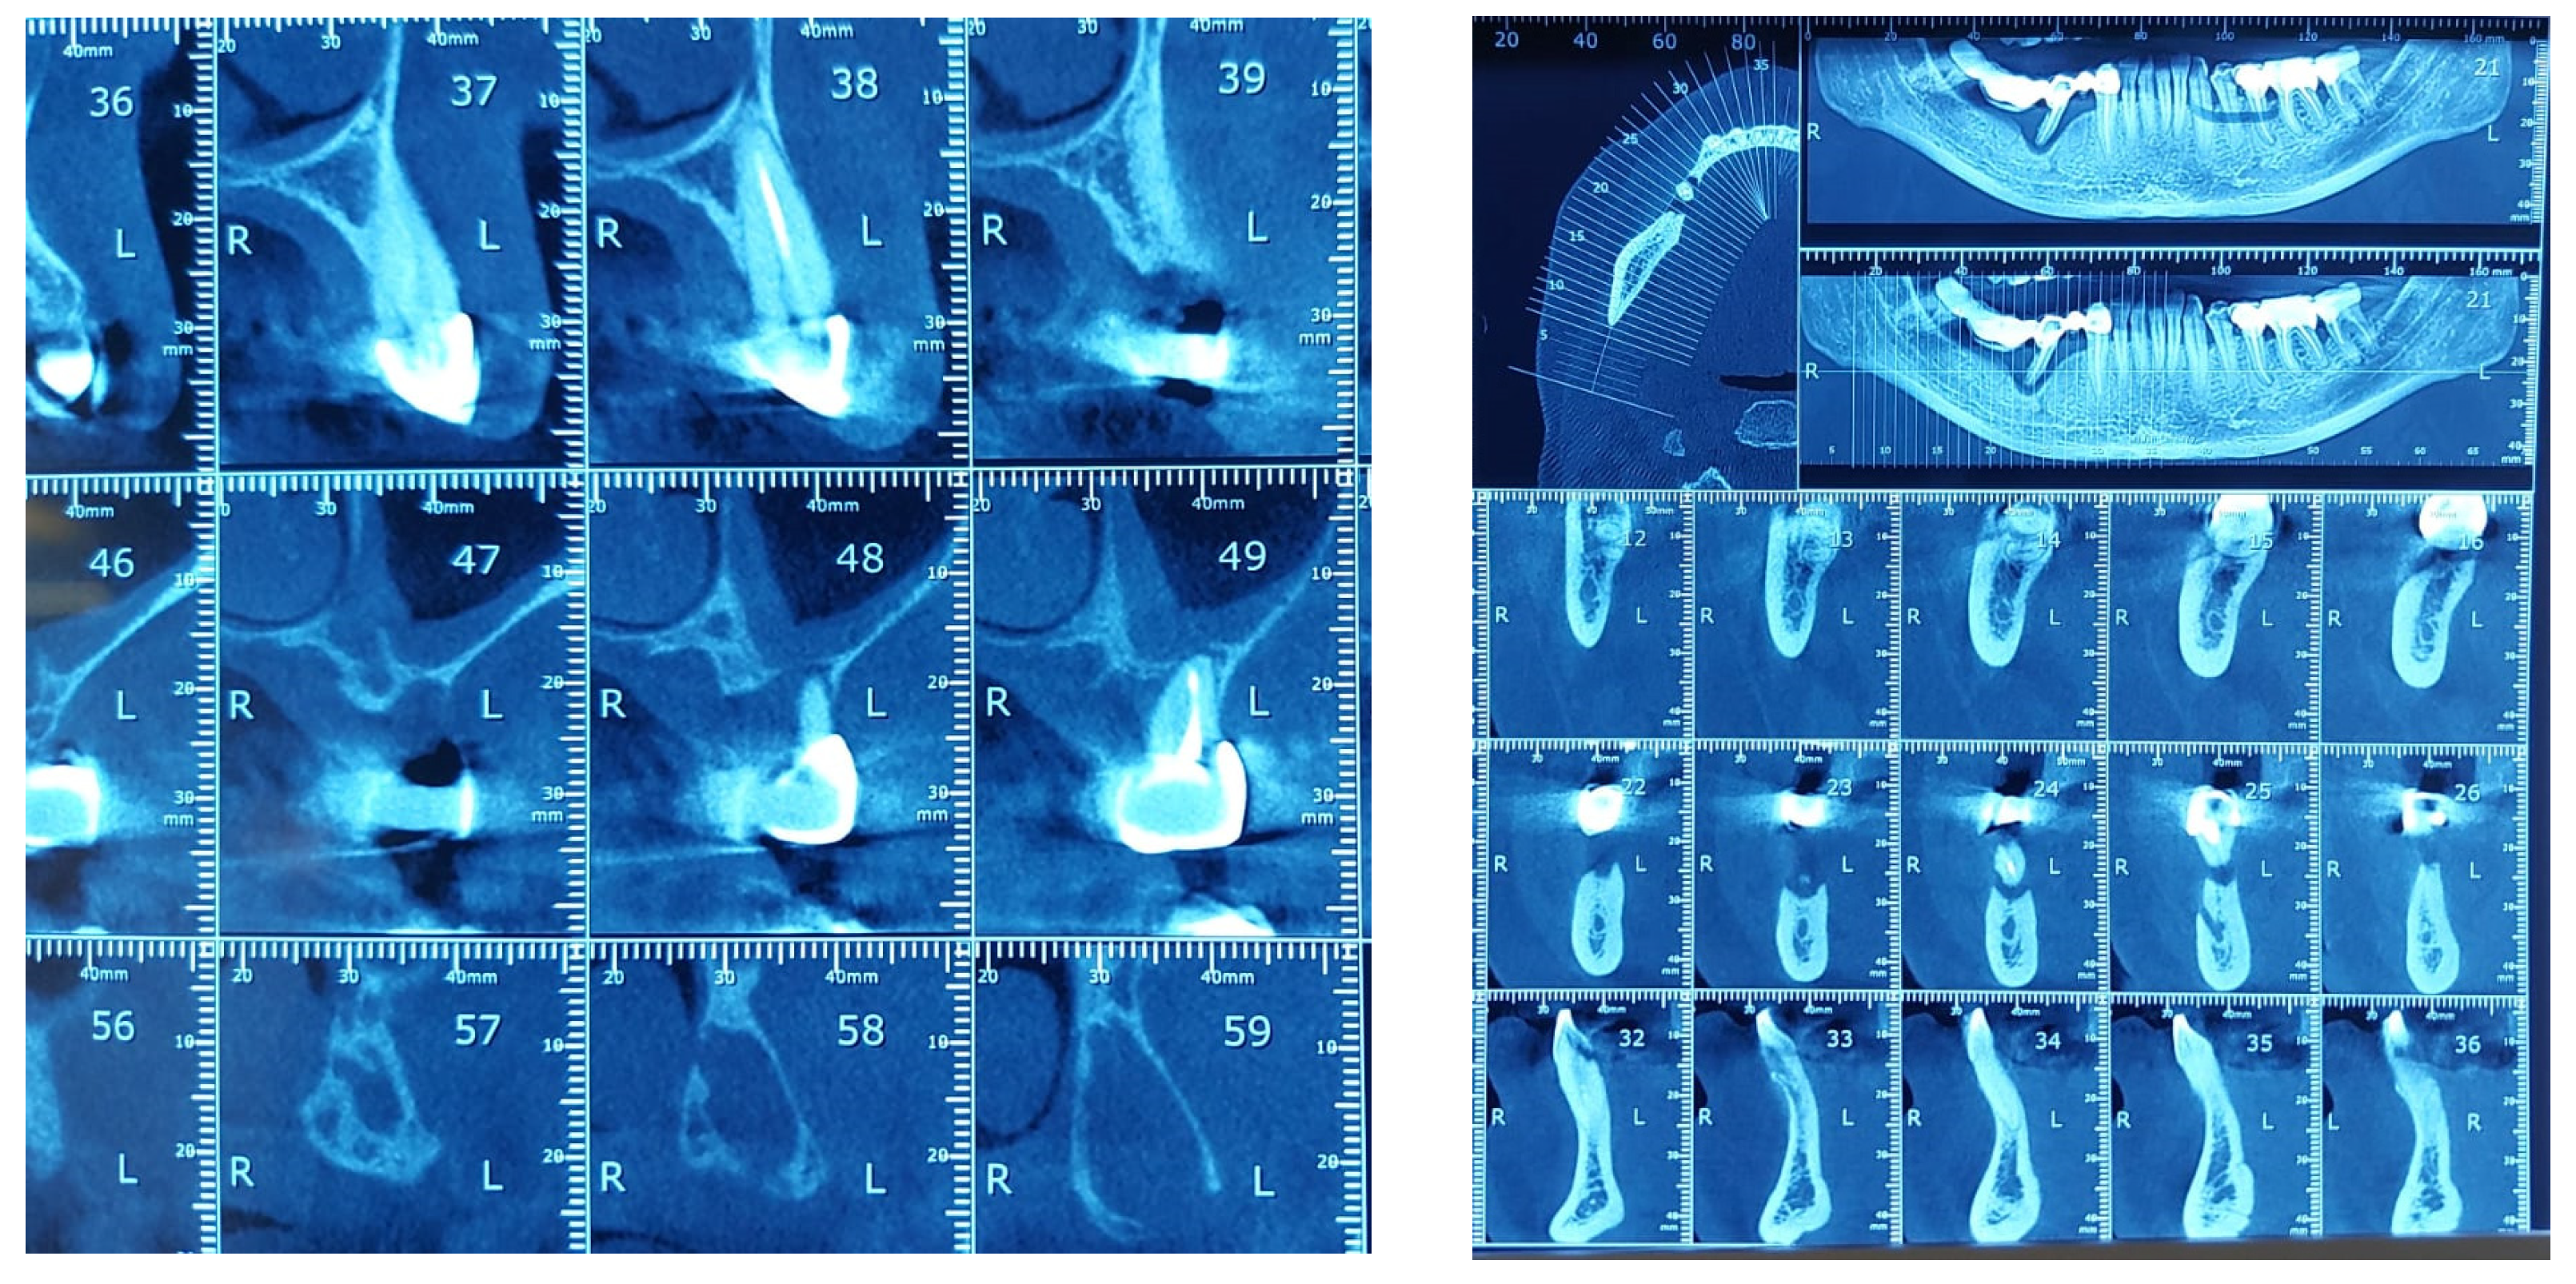

The study found statistically significant correlations between dental mobility and the degree of vertical resorption quantified on CBCT, with relevance to changes at the articular level and reflected by changes in shape or parameter changes during dynamic occlusion. It should also be noted that although the vertical lysis shows significant dimensions, the changes at the articular level captured on CBCT are not significant, which can be explained by the myocene influences at this level (Figure 7).

Figure 7.

Bone Changes in periodontal disease through CBCT. (a) Maxilla CBCT- Bone Changes in periodontal disease; (b) CBCT mandible- Bone Changes in periodontal disease.

Regarding the paraclinical grounds, several sections detected on the CBCT, offering horizontal and vertical selective images with precision, are quite significant. The combination of the two observed resorptions is the basis for the clinical modifications induced by dental mobility. Thus, 25% of the study group followed the specialized imaging evaluations by bringing TMJ tomographs in the paraclinical register and the CBCT of TMJ.